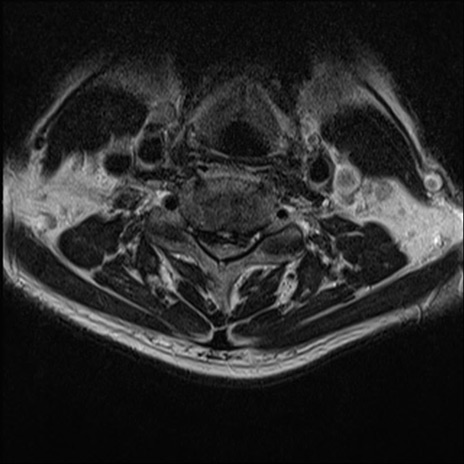

【整形】TIPS症例7 頚椎MRI T2WI(横断像)

頚椎MRI

矢状断像と横断像